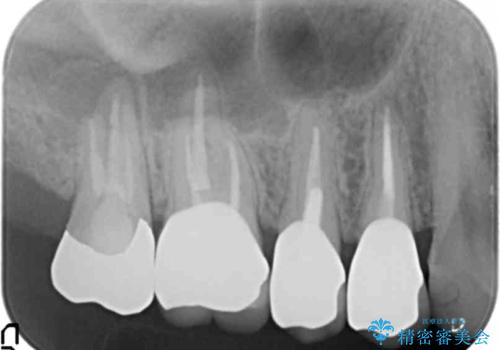

- 歯にものがつまり、以前治療したクラウンの見栄えの悪さの改善を求めて来院されました。

歯ぐきとの境目が、クラウンでしっかりと覆われていないため精密なセラミッククラウンで機能性を回復していきます。

精密なセラミッククラウン製作には、シリコン印象などを用いた精密な型取り、クラウンの製作が大切です。